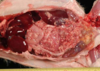

What is the etiological agent associated with Tyzzer’s Disease?

Clostridium piliforme

Tyzzers (gerbils, hamsters, mice)

Tyzzer’s disease – Clostridium piliforme

- “pick-up sticks” on pathology

- Clinical signs – death, dehydration, unkempt, diarrhea, etc.

- Diagnosis – often at necropsy with necrotic hepatic foci and intestinal lesions

- Predetermining factors – over crowding, poor sanitation, over heating, parasites, poor diet

- Treatment – supportive

Tyzzer’s disease – Clostridium piliforme